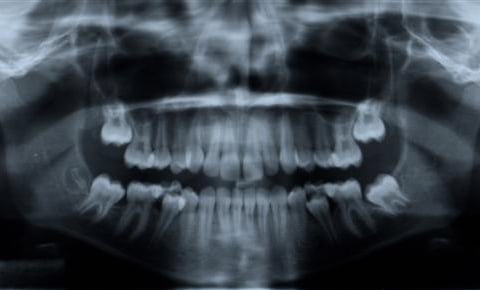

Digital Panoramic X-Rays

A panoramic x-ray is capable of providing a very detailed image of the entire mouth. This includes the teeth, jaw, sinuses and TMJ. It allows the doctor to see how everything looks and can compare how everything is working in relation to each other.